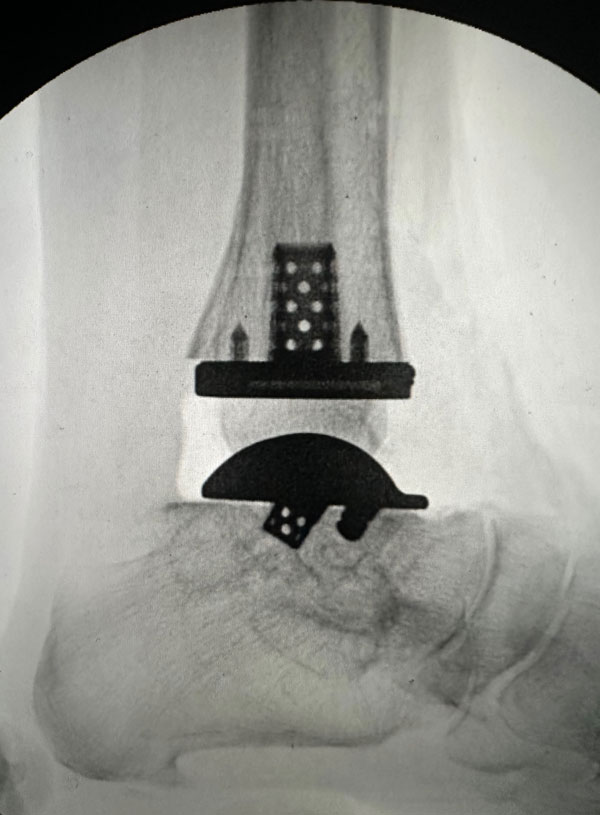

Exactech’s Vantage Ankle 3D and 3D+ tibial implants provide surgeons with tibial stem heights from 10 to 30mm and the added benefits of 3D printing. Additive manufacturing creates a surface that mimics the trabecular nature of cancellous bone. Along with the 3D-printed surface, the implants also feature spiked pegs and a tall sharp central cage, with growing diameters, to aid with initial fixation.

“After several years of developing the 3D+ tibial component with the outstanding Exactech engineers and other design team surgeons, Jim, Jim [Lachman] and I are pleased how the new tibial components and instrumentation seamlessly melded with the existing talar component options. The additive manufacturing, and the press-fit pegs and augmented central cage afford satisfying initial tibial component stability. Particularly exciting is how the intuitive instrumentation allows for reliable and reproducible insertion of a stemmed tibial component through a routine anterior ankle surgical approach.”